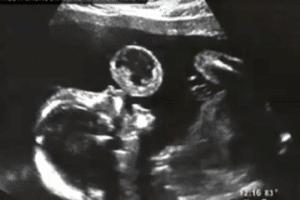

Ultrasonido muestra bebé con una burbuja arriba de sus labios; los médicos quedan en shock cuando descubren de qué se trataba

Tammy, de Miami, USA, había ido por un control y un ultrasonido de rutina cuando los médicos capturaron las imágenes de la bebé con lo que parecía una burbuja justo arriba de sus labios.

La burbuja, lamentablemente no estaba llena de aire; se trataba de un tumor conocido con el nombre de Teratona.

El tumor tenía el tamaño de una pelota de tenis, y según el Dr. Quinteros, quien la atendió y es oriundo de Venezuela, el mayor miedo es que el tumor crezca sin control y que se produzcan sangrados en el feto. Aunque este tipo de tumor no son comunes, pueden presentarse en uno de 35.000 a 200.000 embarazos.